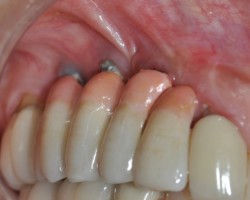

Avant-Après :

Maintenance péri-implantaire

Détartrage des prothèses avec les inserts PerioSoft

Polissage des surfaces avec la buse perio maintenance et poudre perio AIR-N-GO easy

Débridement des spires avec les inserts ImplantProtect et polissage ciblé avec la buse perio et poudre perio AIR-N-GO easy

- Prévention et traitement de la mucosite

- Traitement chirurgical de la péri-implantite

- Maintenance